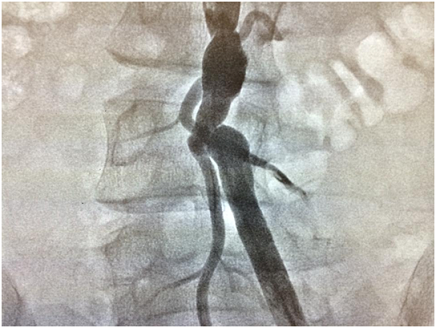

Sağ ümumi qalça arteriyasının anadangəlmə olmaması və aorta bifurkasiyası ilə sol ümumi qalça arteriyasının fibromuskular displaziyası yoxsa Takayasu arteriiti? Dərc edilib: Cild 1, Nömrə 6, 2014 / Nəşr tarixi: 23.08.2014

Firdovsi İbrahimov, Şəxanə Ələsgərli